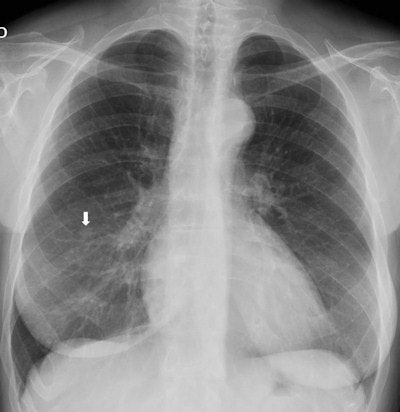

Top: Follow-up imaging of a 72-year-old woman. Preoperative x-ray for skin melanoma. Posteroanterior chest radiography in the upright position shows one suspected pulmonary nodule in the right lung (arrow). Bottom: Digital tomosynthesis image clarifies that the same opacity corresponds to a focal sclerosis within the poster arch of a right rib (arrow). Readers provided a confidence score of 1.Tomography findings were proven by CT (114 patients), chest x-ray during follow-up (105), or histology (18). The final diagnoses included 77 pulmonary opacities, 26 pulmonary scars, 12 pleural lesions, and 122 pulmonary pseudolesions. Tomosynthesis versus chest x-ray presented a higher (p < 0.05) sensitivity (92% vs 15%), specificity (91% vs 9%), overall accuracy (92% vs 12%), and diagnostic confidence (area under ROC, 0.997 vs 0.619). Mean effective dose of chest x-ray vs tomosynthesis was 0.06 vs 0.107 mSv (p < 0.05).